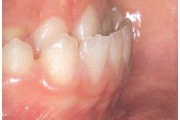

Esimese jäävmolaari ektoopiline lõikumine

Ravijärgne seis. Jäävhammas on täielikult lõikunud.

) Röntgenülesvõte. Ülemise esimese jäävmolaari lõikumine on takistatud 2. piimamolaari tõttu